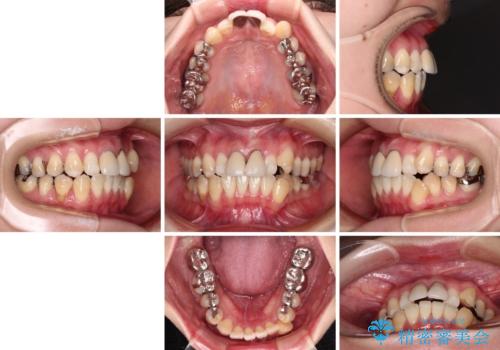

- 前歯のデコボコとセラミッククラウン周りの黒い縁を気にして来院された患者様です。

ワイヤー装置、マウスピース、どちらの装置でも治療は可能でしたが、マウスピース矯正の自己管理の煩わしさを懸念され、ワイヤー装置にて矯正治療を行うこととしました。

前歯の黒い縁は、矯正治療後にオールセラミッククラウンにて改善することとしましたが、いち早く目立たなくしたいとのことで、事前に矯正治療用仮歯に置き換えてから矯正治療を開始しました。

前歯を早々に仮歯に置き換えたことで、矯正治療に意欲的に臨んでくださいました。

口元が前方に突出することもなく、綺麗に仕上げることができました。